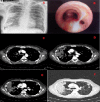

(A) Chest x-ray on presentation. (B) Flexible bronchoscopy showing tracheal bronchus. (C) CT chest (mediastinal window) showing no significant station 2 lymph nodes. (D) CT chest (mediastinal window) showing no significant station 4 lymph nodes. (E) CT chest (mediastinal window) showing no significant station 7 lymph nodes. (F) CT chest (lung window) showing interstitial lung shadowing in the right middle lobe.